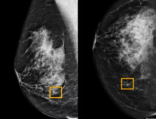

• 医疗人工智能|清华、协和等单位开发乳腺癌AI诊断工具,可准确识别恶性肿瘤 5年前

近年来,随着人工智能技术的发展,越来越多的人工智能算法应用于医学图像领域,并深刻地改变了医学影像的发展,从一开始仅仅提供...

恶性肿瘤 乳腺癌 AI诊断